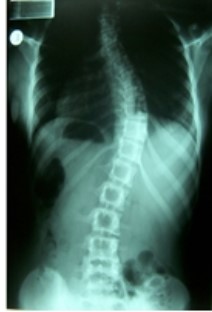

Galerija 1 Osnovne informacijeO namaDjelatnostiPreporuka za VasKako do nasPovoljna cijena ortopedskih pregledaGostovanje u emisiji Bez uputniceVažnost ultrazvučnog pregleda dječjih kukovaGalerija 1Galerija 2Galerija 3.1.Galerija 3.2.Galerija 4Galerija 5Cerebralna Paraliza i Ortopedske IntervencijeKako se pripremiti za manji operacijski zahvatSavjeti ortopeda za najčešće sportske ozljede i njihova prevencijaKralježnica: Važnost ranog prepoznavanja deformiteta i bolesti kralježniceKoljenski zglob: Razlozi brzog trošenja hrskavice, čestog ozljeđivanja i mogućnosti liječenjaPonude i popustiKarta - kako do nas?KomentariKontakt Galerija 1 Objavljeno: 18.9.2023. 15:20